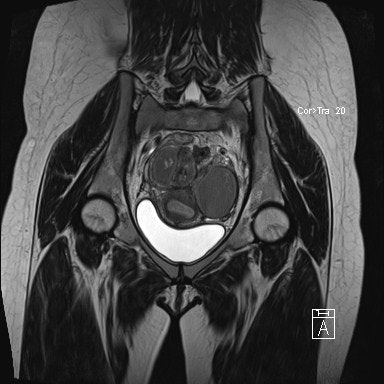

The study included 31 patients who were imaged using a 1.5-tesla MR system (Magnetom Avanto, Siemens Healthcare). They imaged in the supine position with a phased-array surface coil and received 20 mg of intravenous hyoscine butylbromide (Buscopan, Boehringer Ingelheim) just prior to imaging to minimize bowel peristalsis. High-resolution 3D T2-weighted images were obtained in the coronal plane.

Two experienced radiologists independently assessed image quality and disease extent in the 31 patients. Both were blinded to patient identity, previous imaging, and menstrual status. Interobserver agreement was assessed using the kappa (κ) test.

The researchers found moderate interobserver agreement for image quality of T2-weighted imaging (κ = 0.475, p < 0.001) and substantial agreement for T1-weighted imaging with fat saturation (κ = 0.733, p < 0.001).

Site-specific interobserver agreement was moderate to excellent (i.e., κ > 0.41) for the majority of locations, with the only poor interobserver agreement demonstrated at the vesicouterine pouch (κ = -0.0053). The only poor interobserver agreement demonstrated on the menstrual scans was at the rectovaginal septum (κ = -0.03).

Overall though, there was no statistically significant difference in image quality between the menstrual and nonmenstrual scans at all imaged sites (p > 0.255 for all). Also, there was no significant difference between the menstrual and nonmenstrual groups with regard to disease certainty -- all p-values were greater than 0.481.

"Findings suggest no significant differences in image quality, disease extent, or disease severity between menstruating and nonmenstruating MR, thus timing of pelvic MR for assessment of endometriosis need not be influenced by the menstrual cycle," the study authors wrote.